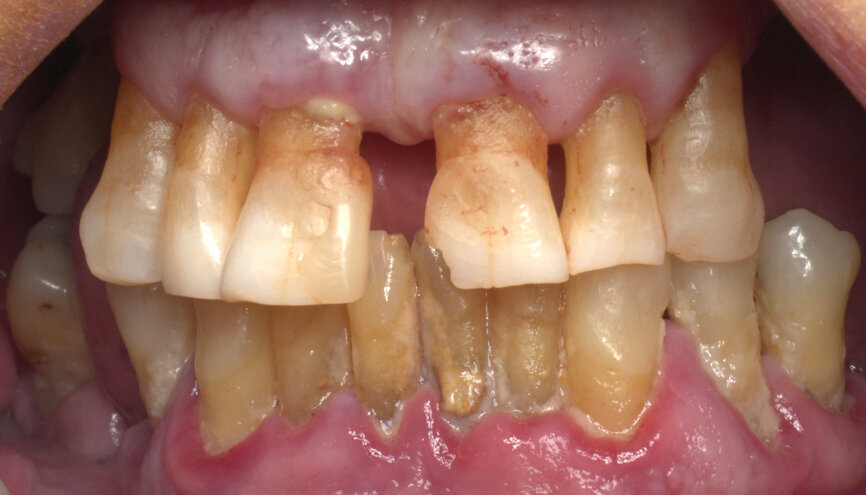

A 68-year-old patient with no medically relevant history and hopeless dentition was referred by his periodontist. A panoramic radiograph and dental CT scan were taken to evaluate the bone availability, disposition and density (Figs. 1 & 2). After the different treatment options were discussed, and in view of the patient’s overall dental, social and financial situation, an implant treatment with a same-day fixed temporary restoration was the first choice for both the dental team and the patient.

The surgery was performed under local anaesthesia and with patient monitoring by an anaesthesiologist using conscious intravenous sedation with midazolam and pulse oximetry monitoring. Removing failing teeth was the first task, keeping in place those teeth with less mobility and in strategic positions to maintain antagonist contacts, and trying to keep the same preoperative bite (Fig. 4).